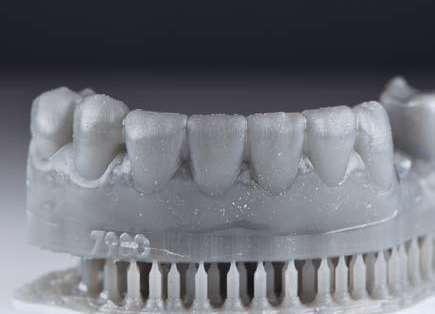

Además, lo combinaremos con unas carillas inyectadas inferiores también planificadas digitalmente y sin tallado, para crear una armonía y equilibrio con la parte superior.

Para la arcada inferior se optó por unas carillas inyectadas, completamente respetuosas con los tejidos, que nos permiten mejorar la apariencia de los dientes y dar así una mayor armonía con la parte superior. Al ser también planificadas digitalmente aseguramos que lo que colocamos en boca sea una fiel reproducción del diseño previamente aceptado por el paciente y el profesional.

La tecnología digital permite lograr el equilibrio de espesores ideal para cada caso, así como un eje de inserción adecuado. Todo esto permite dar una garantía de longevidad a las restauraciones planificadas.

En este caso se realizó una preparación previa a la preparación guiada en los márgenes y zonas interproximales, para camuflar el sustrato y dar una correcta inserción; y posteriormente se utilizaron unas guías de tallado diseñadas digitalmente para obtener los resultados precisos y predecibles que requería el caso.

La preparación previa junto a la preparación guiada, resultaron en un equilibrio ideal para los espesores mínimos que requería el caso. Se realizó una prueba en seco para valorar el ajuste final de las restauraciones.

Para cementar las carillas y evitar movimientos no controlados y una incorrecta cementación, utilizaremos una guía de posicionamiento simultáneo, esta guía no es de cementación en bloque ya que las carillas están perfectamente individualizadas. Únicamente sirven para llevar a la boca del paciente las carillas y cementarlas de una forma 100% segura, evitando el estrés que genera un posible movimiento durante la cementación y acelerando los tiempos de trabajo.